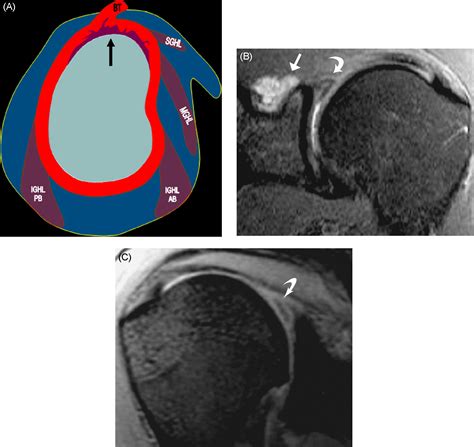

An MRI is a non-invasive imaging technique that uses magnetic fields and radio waves to produce detailed images of the body’s internal structures. For diagnosing a Slap Tear MRI, the scan provides high-resolution images of the shoulder joint, allowing radiologists to identify tears in the labrum and other soft tissue injuries.

Slap Tear MRI scans are particularly useful for diagnosing SLAP tears because they provide clear images of the labrum and surrounding structures. However, interpreting the results requires expertise, as SLAP tears can be subtle and easily missed.

Interpreting the results of a Slap Tear MRI involves a thorough examination of the images by a radiologist. Key findings that indicate a SLAP tear include:

• Abnormal signal intensity within the labrum, suggesting a tear.

• Displacement or detachment of the labrum from the glenoid.

• Fluid or contrast agent extending into the tear, highlighting the extent of the injury.

• Associated injuries, such as rotator cuff tears or biceps tendon pathology.

Radiologists use specific criteria to classify SLAP tears based on their appearance on MRI images. For example, a Type II SLAP tear may show detachment of the labrum and biceps tendon from the glenoid, while a Type IV tear may exhibit a displaced flap of tissue.